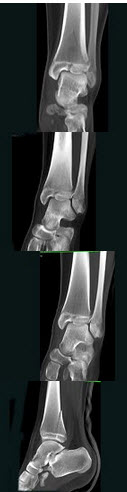

62、单项选择题

男,15岁,从楼梯上滑倒,足部扭伤,结合图像,最可能的诊断是()

A.腓骨骨折

B.胫腓骨骨折

C.胫骨骨折

D.距骨骨折

E.跟骨骨折